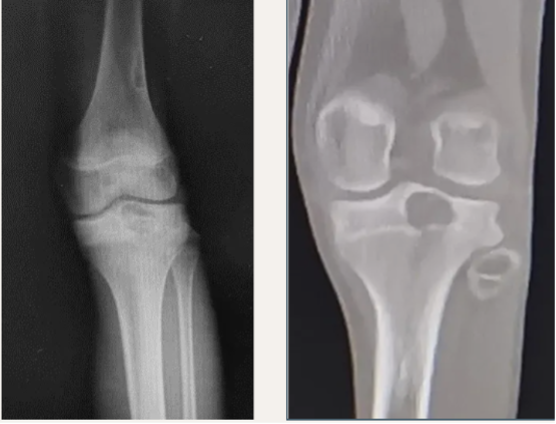

软骨母细胞瘤(chondroblastoma)为良性肿瘤,占所有骨肿瘤的比例不到1%,常发生于儿童和青少年,好发于长骨的骨骺:股骨、肱骨和胫骨。组织学上,软骨母细胞瘤由密集排列的软骨母细胞、多少不一的破骨细胞样巨细胞以及钙化的软骨样基质构成,软骨母细胞瘤的瘤细胞核中可见H3.3 K36M阳性表达。治疗上彻底刮除并辅助瘤腔处理是主要治疗手段,由于病变常位于骺板附近,手术治疗可能影响骨骼发育。